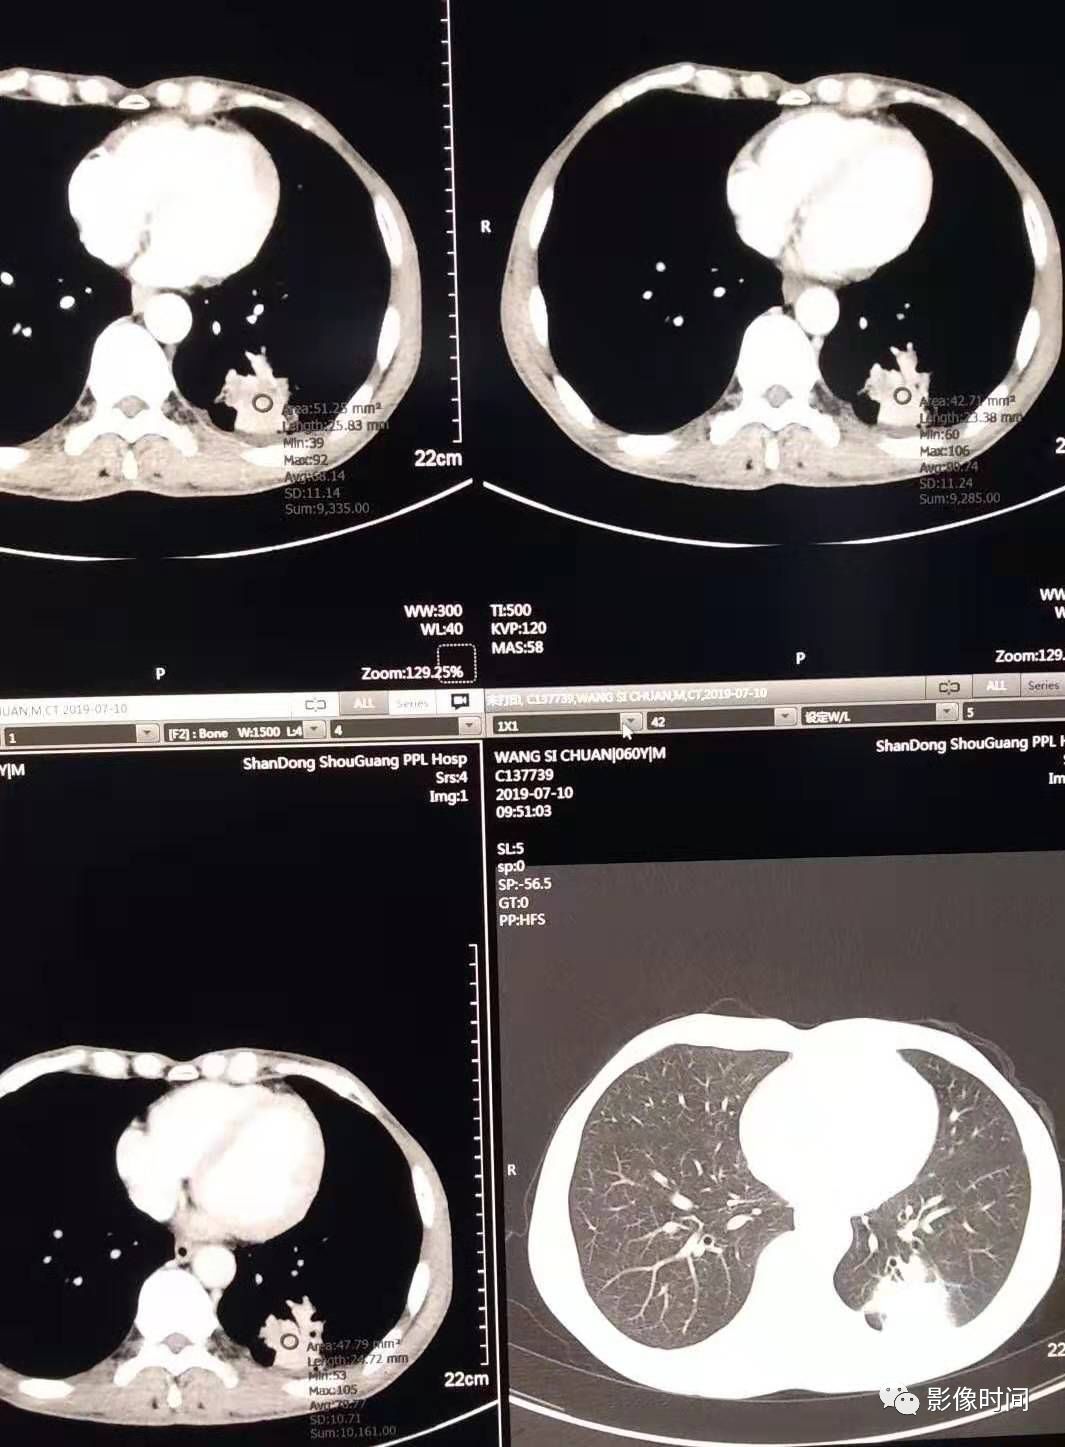

肺部病灶 | 炎症还是癌症,你可分得清?

肺部病灶炎症还是癌症你分得清吗